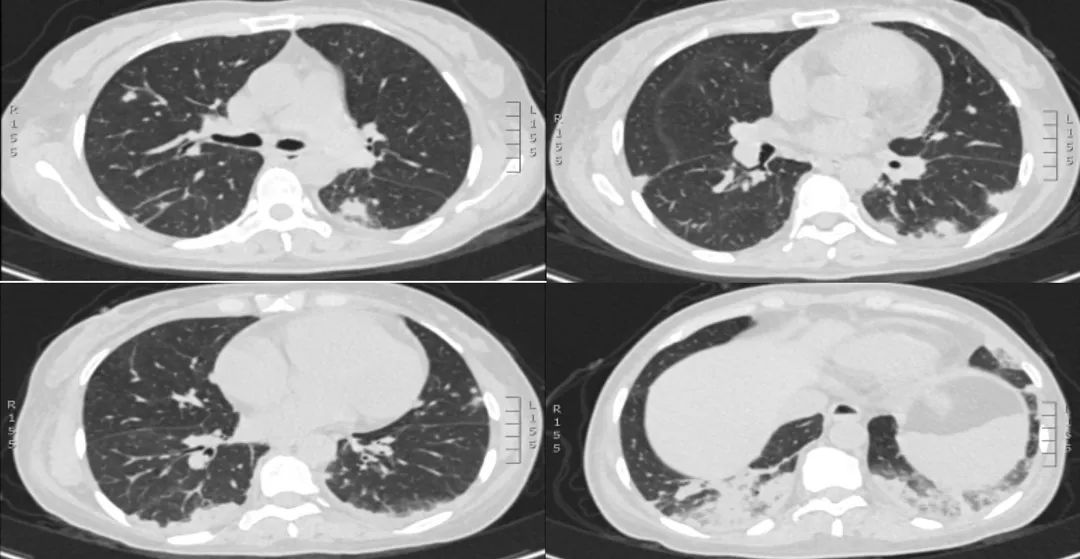

主诉:间断发热伴干咳、气短10天

现病史:入院10天前洗澡后着凉,发热39℃,干咳,略气短。静滴阿奇霉素3天,症状改善。停药一天,再次发热,38℃,气短加重。再次应用阿奇霉素及头孢类抗生素治疗效果不佳。当地医院检查D二聚体增高,血小板减少;肺动脉CTA发现肺栓塞和肺浸润影。当地诊断「肺栓塞,肺炎」,因血小板过低及进行性下降未予抗凝。病来患者无头晕头痛、无晕厥、无恶心呕吐、无腹痛腹泻,饮食睡眠差,体重较前无明显变化。

入院查体:T 36.6℃,P 110次/分,R 24次/分,Bp115/81mmHg。身高:158cm,体重50kg,BMI 20.03。神志清,一般状态可,呼吸略促、贫血貌,浅表淋巴结未触及。双肺听诊左上肺呼吸音粗,双下肺呼吸音弱,可闻及湿啰音。心律齐,P2>A2,胸部左下缘可闻及收缩期杂音。腹软,无压痛、反跳痛及肌紧张。左手肿胀,大鱼际处可见结痂、无破溃。右下肢凹陷性水肿。周身少量淤斑和紫癜。

血气分析:PH:7.47,PaO2:58mmHg(双鼻导管吸氧7L/min)PaCO2:32mmHg,HCO3-: 22.3mmol/L血常规:WBC 13.22×10^9/L,NE 7.31×10^9/L(3.5-9.5),NE% 55.3%,EO 2.8×10^9/L(0.02-0.52),EO% 21.2%,Hb 79g/L(115-150),PLT 6×10^9/L(125-350)尿常规:蛋白 3+, 潜血2+, 尿系列:RBC 3-7/HP, 异形80%CRP 75.7mg/L(0-5),PCT 0.514ng/ml(0-0.046),ESR 25mm/h凝血四项:PT15.9s(11-14.3),凝血酶原活动度 70%(80-120),PT-INR 1.26,APTT 42.6s(32-43),Fg 1.54g/L(2-4)D-dimer>20ug/ml(0-0.5)生化指标:ALB 21.1g/L(40-55),ALP 208U/L(50-135),GGT 119U/L(7-45),血糖正常,余AST、ALT、胆红素、肌酐、离子均正常。心脏指标:BNP 173pg/ml (0-100),cTnI 0.036ng/mL (0-0.026)2019-6-13肺动脉CTA